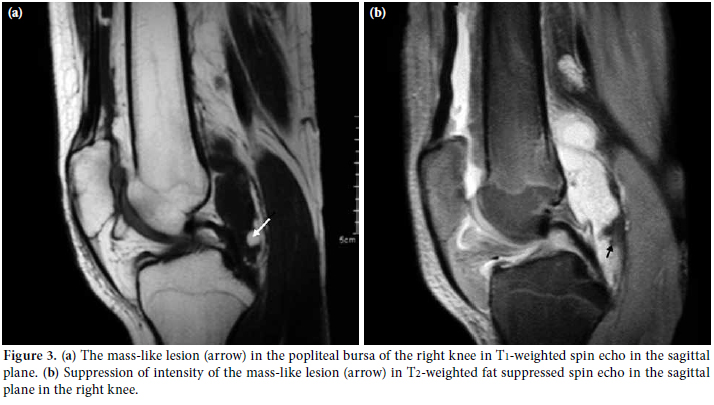

Magnetic resonance imaging revealed a large effusion and numerous frond-like projections which were prominent in the suprapatellar compartment of right knee. The intensity of these frond-like synovial projections, which were suppressed in fatsaturated sequences, was similar to the intensity of fat (Figures 2a, b). An effusion and a mass-like lesion were also detected in the popliteal bursa of the right knee. (Figures 3a, b) In addition, mild osteochondral changes occurred in both knees which were more pronouced on the right side (Figure 2a). Suprapatellar effusion was also detected in the left knee. No meniscal or ligament pathology was detected in either knee.

Because of its histological nature, MR imaging findings of LA are accepted as typical and help us for a confident preoperative diagnosis. Magnetic resonance imaging is highly accurate for the identification and characterization of LA and is the best imaging modality and the cornerstone of the preoperative diagnosis.[13-15] Villous synovial proliferations with a signal intensity similar to that of fat in all sequences, mass-like subsynovial deposits, large effusions, potential demonstration of associated chemical shift artifact at the interlace of the synovial lesion and the effusion, and no evidence of hemosiderin deposition are included in the MRI results identifying LA.[1,3,5,7] These typical results allow for a confident preoperative diagnosis and can exclude other possible clinical and radiological mimickers,, such as synovial osteochondromatosis, pigmented villonodular synovitis, synovial hemangioma, and synovial lipoma.[14,15] In our cases, there was prominent suprapatellar effusion and synovial hypertrophy. In the fat-suppressed MRI, the fatty nature of the focal areas was more clearly demonstrated. Pigmented villonodular synovitis (PVNS), synovial chondromatosis, RA, intraarticular lipoma, and synovial hemangiomas should be considered in the differential diagnosis of LA as they usually present with painless synovial thickening and effusion. In PVNS, there are focal areas of hemosiderin deposits characterized by significantly low signal intensity in both T1- and T2-weighted images. There is also contrast enhancement in PVNS. Synovial chondromatosis is defined by multiple cartilaginous nodules. These nodules have intermediate-to-high signal intensity in T2-weighted images and low-tointermediate signal intensity in T1-weighted images. Synovial hemangiomas appear as either intraarticular or extraarticular lesions of intermediate signal intensity on both T1- and T2-weighted images. There might be areas of focal low signal intensity. This suggests calcified phleboliths or fluid void in abnormal vessels. Synovial lipoma is another disorder that must be considered in differential diagnosis. In this disorder, MRI reveals a solitary, localized mass of adipose tissue without synovial changes. Chronic rheumatoid arthritis shows intermediate signal intensity on T1-weighted images and relatively decreased signal intensity on T2-weighted images within the synovium. This is associated with the formation of pannus. Lipoma arborescens is usually located in the suprapatellar recess. In contrast, PVNS, synovial hemangiomatosis, and lipoma are usually located in the infrapatellar fat pad of Hoffa.[1,10,17-19] According to the clinical and radiological/laboratory examinations and the MRI findings, we concluded that LA was the correct diagnosis in our cases. Although we referred our patients to orthopedics department for surgical synovectomy aiming not only to establish LA diagnosis conclusively, but also to treat the disease, family didn’t accept the surgical synovectomy. Therefore LA diagnosis could not be confirmed histologically in our patients, though MR imaging findings were highly suggestive of LA in both cases.